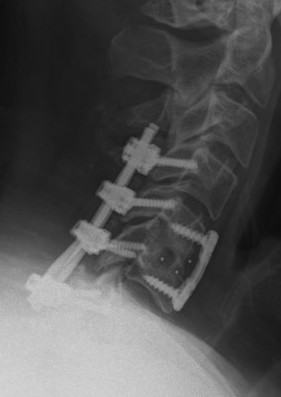

ACDF

Indication

Anterior cord compression

Single or double level compression

Kyphotic deformity

Advantages

Removes entire disc

Maintain / restore lordosis

Disadvantages

Difficulty decompressing the nerve roots in foramen

Difficult to decompression vertebral bodies

Relatively contra-indicated with OPLL